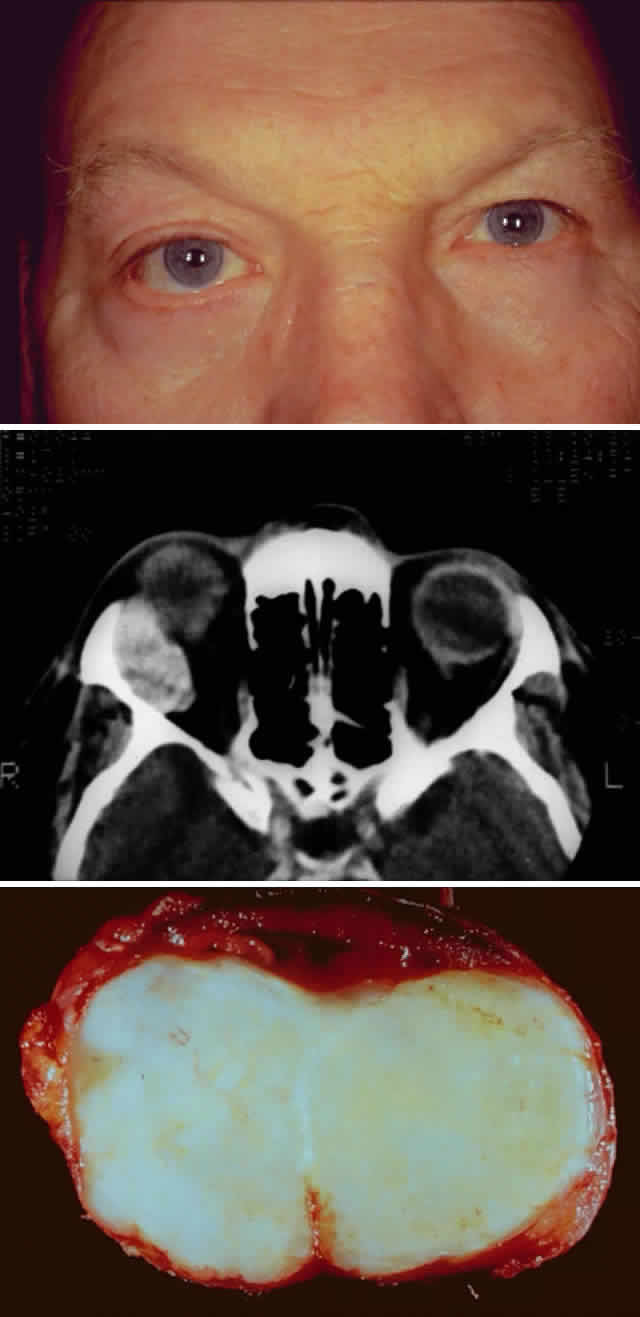

The incidence of pleomorphic adenomas is equal for both genders, and these neoplasms usually present in the fifth decade of life.15,16 Symptoms may vary depending on the location of the tumor within the lacrimal gland.15,36,37 Pleomorphic adenomas usually involve the orbital lobe and present with symptoms of painless, progressive, nonaxial proptosis and restricted ocular motility (Fig. 4A). These symptoms are typically present for more than 1 year.9,13–15,22 A round or oval mass is present within the lacrimal gland fossa. Smooth erosion (bone modeling) without invasion or destruction of bone is almost always visualized on computed tomography9,15,22 and indicates the slow growth of this disorder (see Fig. 4B).

Fig. 4. A 47-year-old man with a 2-year history of slowly progressive, nonaxial proptosis secondary to a benign pleomorphic adenoma. A. Clinical photograph demonstrating proptosis of the right eye with asymmetric fissures and mild inferior and medial displacement of the globe. B. Computed tomographic image of the pleomorphic adenoma. Note the smooth bone erosion of the lacrimal fossa. The lesion does not extend beyond the orbital rim. C. Photograph of the gross specimen, which has been cut to demonstrate its solid consistency contained within a “pseudocapsule.”